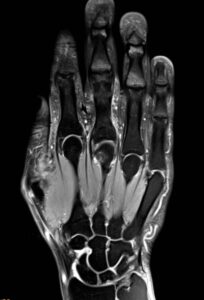

Anatomisch gesehen besteht die Hand aus 37 Knochen, die über unterschiedlich geformte Gelenke in Verbindung stehen. Hinzu kommen Bänder, Sehnen, Sehnenscheiden, Muskeln und Gelenkkapseln, die allesamt sowohl die einzigartige und filigrane Beweglichkeit als auch die Stabilität von Handwurzel und Fingern gewährleisten. Doch jedes dieser Elemente kann bei einer Schädigung ganz eigene Beschwerden hervorrufen – kein Wunder, dass Fingerschmerzen ein Krankheitsbild mit vielen Gesichtern ist.

Bei der Magnetresonanztomographie handelt es sich um ein bildgebendes Verfahren, bei dem – im Gegensatz zu Röntgen- oder CT-Bildern – das Körperinnere ohne den Einsatz von Röntgenstrahlen dargestellt werden kann. Stattdessen kommen starke Magnetfelder und Radiowellen zum Einsatz. Der Körper wird dabei schichtweise gescannt.

Das bedeutet, dass zunächst in sehr kleinen, regelmäßigen Abständen zweidimensionale Schnittbilder durch Ihren Körper aufgenommen werden – Schicht für Schicht. Anschließend können diese am Computerbildschirm betrachtet werden, was einen dreidimensionalen Eindruck vermittelt. Zusätzlich ist allerdings auch eine rechnerische 3D-Rekonstruktion der Bilder am Computer möglich, sodass diese anschließend aus jedem beliebigen Blickwinkel betrachtet werden können.

Die MRT besticht dabei durch ihr Detailreichtum und den hohen Weichteilkontrast. Insbesondere bei Untersuchungen der Hand bzw. der Finger ist dies von besonderer Bedeutung, denn hier müssen auch kleinste Strukturen darstellbar sein. Zur Aufnahme der Bilder gibt es MRT-Geräte mit unterschiedlich starken Magnetfeldern. Die sogenannte Feldstärke wird in der Einheit Tesla (T) angegeben.

In der Diagnostik von Erkrankungen von Hand und Fingern werden 3-Tesla-Scanner gegenüber 1,5-Tesla-Geräten bevorzugt. Durch die höhere Feldstärke ist das bei der Magnetresonanztomographie zur Bildaufnahme gemessene Signal stärker. Dies wiederum bietet die Möglichkeit einer höheren Auflösung.